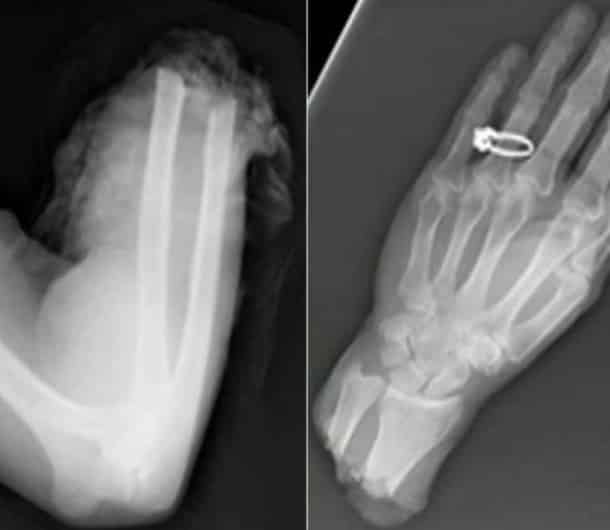

Accident, incident de pistolet à clous ou introductions douteuses de choses douteuses dans des parties douteuses de leur corps…voilà un petit aperçu de ce que voient les médecins au quotidien…

Certaines radiographies sont impressionnantes mais relèvent d’accidents…d’autres en revanche…